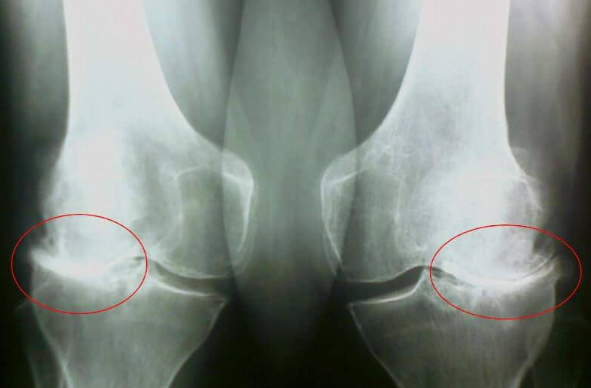

Pogledajte ove slike, možete vidjeti da na desnoj slici nema zglobnog prostora, kosti se trljaju jedna o drugu, izazivajući jak bol. I ovaj proces je veoma teško zaustaviti! Za par godina čovek će postati invalid i neće moći da se služi.